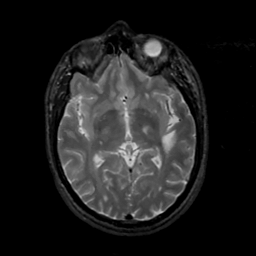

MR Study #6, March 17, 1991 -- Slice #24